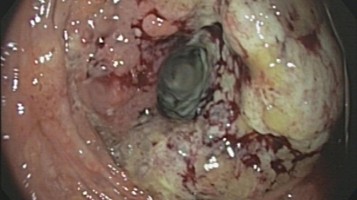

Ösophagogastrale Karzinome: "Highlight des Jahres" und mehr

Sowohl bei der zielgerichteten Behandlung als auch der Immuntherapie von resezierbaren Karzinomen des Magens und des gastroösophagealen Übergangs gibt es neue Daten. Ein Highlight: Die Ergebnisse zum Gesamtüberleben der Phase-III-Studie MATTERHORN.

Ältere Frau fasst sich an die Brust/© Jelena Stanojkovic / Stock.adobe.com (Symbolbild mit Fotomodell), Eine ältere Frau riecht an einem Basilikumblatt/© Halfpoint / Stock.adobe.com (Symbolbild mit Fotomodell), Person setzt DNS-Probe in Maschine ein/© Vit Kovalcik / stock.adobe.com, Schwangere/© Yakobchuk Olena / Stock.adobe.com (Symbolbild mit Fotomodell), Mann raucht Joint/© Daniel Sierralta / Westend61 / stock.adobe.com (Symbolbild mit Fotomodell), Blut in Toilette/© stylefoto24 / stock.adobe.com, Ultraschall bei einem älteren Patienten/© Alex Potemkin / Getty Images / iStock (Symbolbild mit Fotomodellen), Person hält Tablette und Glas/© bilderstoeckchen / stock.adobe.com (Symbolbild mit Fotomodell), Pulsoximeter wird an Finger angeschlossen/© Yakobchuk Olena / stock.adobe.com, Frau hält sich eine Brustseite nach Mastektomie/© chotiga / Stock.adobe.com (Symbolbild mit Fotomodell), Frau in der Menopause mit Hormonpflaster/© Anchiy / Getty Images / iStock (Symbolbild mit Fotomodell), Ältere Person sortiert Medikamente/© Przemek Klos / stock.adobe.com (Symbolbild mit Fotomodell), Frau hat Bauchschmerzen nach dem Konsum von Brot/© weyo / stock.adobe.com (Symbolbild mit Fotomodell), Älterer Mann mit Tabletten in der Hand/© vorDa / Getty Images / iStock (Symbolbild mit Fotomodell), Frau hält Tabletten-Blister und Beipackzettel in der Hand/© Vladimir Vladimirov / Getty Images / iStock (Symbolbild mit Fotomodell), Medikamente und Medikationsplan/© Photographee.eu / stock.adobe.com, Adipösem Jungen wird Blutdruck gemessen/© New Africa / stock.adobe.com (Symbolbild mit Fotomodell), Frau unkenntlich fasst sich ans Knie/© Pornpak Khunatorn / Getty Images / iStock (Symbolbild mit Fotomodell), Blutabstrich der chonisch lymphatischen Leukämie/© jarun011 / Getty Images / iStock, Endoskopische Befunde des Magenkarzinoms/© Probst, A., Messmann, H. / all rights reserved Springer Medizin Verlag GmbH, Hand hält Laborröhrchen/© Kunstzeug / stock.adobe.com (Symbolbild mit Fotomodell), Radiologin richtet Mammographiescreening ein/© LIGHTFIELD STUDIOS / stock.adobe.com (Symbolbild mit Fotomodellen), Mann hält Tablette und ein Glas Wasser in den Händen/© somenski / Fotolia (Symbolbild mit Fotomodell), Diffus großzelliges B-Zell-Lymphom (DLBCL)/© David A Litman / stock.adobe.com, Schwangere misst Blutzucker/© MMPhotography / Getty Images / iStock (Symbolbild mit Fotomodell), Infusion/© georgeoprea9 / Getty Images / iStock, Mann erleidet Schwindel/© Tunatura / Getty Images / iStock (Symbolbild mit Fotomodell), Stereotaktische Strahlentherapie (SBRT) einer solitären ossären Metastase in dem Brustwirbelkörper/© Springer Medizin Verlag GmbH, Hirntumoren sichtbar im MRT/© semnic / Getty Images / iStock (Symbolbild mit Fotomodell), Endobronchialer Befund mit exophytischem Tumor im Bereich des rechten Oberlappens/© Möller, M., Schütte, W. / all rights reserved Springer Medizin Verlag GmbH, Aufziehen einer Spritze/© Eisenhans / Fotolia, Adipöser Mann konsultiert Ärztin/© Halfpoint / stock.adobe.com (Symbolbild mit Fotomodellen), Herpes Zoster am Rücken/© Mumemories / Getty Images / iStock (Symbolbild mit Fotomodell), Einem Mann wird Blut abgenommen/© auremar / stock.adobe.com (Symbolbild mit Fotomodellen), Mann erhält einen CT-Scan /© Mark Kostich / stock.adobe.com (Symbolbild mit Fotomodell), Frau wird Blut abgenommen/© andresr / Getty Images / iStock (Symbolbild mit Fotomodellen), CT-Pulmonalisangiographie/© Das M et al. doi.org/10.1007/s00117-016-0100-3 unter CC-BY 4.0, Eine Frau erhält eine Chemotherapie/© peopleimages.com / stock.adobe.com (Symbolbild mit Fotomodell), Blutentnahme/© fotoblin / Fotolia (Symbolbild mit Fotomodellen), Älter Patient im Klinikbett/© Yakobchuk Olena / stock.adobe.com (Symbolbild mit Fotomodellen), Lungentrainer/© S@photo / stock.adobe.com (Symbolbild mit Fotomodell), Tabletten werden in Hand geschüttet/© O.Farion / Stock.adobe.com (Symbolbild mit Fotomodell), DGIM Podcast-Reihe - Frailty/© (M) David L / peopleimages.com / Stock.adobe.com (Symbolbild mit Fotomodell), akute Sigmadivertikulitis/© Springer Medizin, Pneumocystis-jirovecii-Pneumonie in der CT/© Springer Medizin, Tumorzellen werden von T-Zellen attackiert/© drimafilm / stock.adobe.com, Melanom Nahaufnahme/© selvanegra / Getty Images / iStock (Symbolbild mit Fotomodell), Mann appliziert Salbe auf sein Knie/© Ake Ngiamsanguan / Getty Images / iStock (Symbolbild mit Fotomodell), Kolorektales Karzinom/© Pox, C.P. et al. / all rights reserved Springer Medizin Verlag GmbH, Kolorektale Lebermetastase in Segment II, nahe der linken Lebervene (LHV)./© Sucher, E. et al. / all rights reserved Springer Medizin Verlag GmbH, Hals und Schultern einer sehr mageren Frau/© nielskliim / stock.adobe.com (Symbolbild mit Fotomodell), Infusionstropf im Krankenhaus /© Trsakaoe / stock.adobe.com, Senior nimmt Medikament an/© Yuri Arcurs / Fotolia (Symbolbild mit Fotomodellen), Mehrere Personen erhalten Chemotherapie/© FatCamera / Getty Images / iStock (Symbolbild mit Fotomodellen), Frau mit Kopf- und Bauchschmerzen/© astrosystem / stock.adobe.com (Symbolbild mit Fotomodell), Ältere Frau mit Kopfschmerzen im Bett/© digitalskillet / iStock (Symbolbild mit Fotomodell), Störung der Lidhebung bei Myasthenia gravis/© Alessandro Grandini / stock.adobe.com (Symbolbild mit Fotomodell), Cannabisarzneimittel/© [M] Rocky89 / Getty images / iStock, Eine Person sitzt müde im Bett und stützt den Kopf auf die Hände/© demaerre / Getty Images / iStock (Symbolbild mit Fotomodell), Junger Mann bekommt einen Zugang gelegt/© Tyler Olson / Stock.adobe.com (Symbolbild mit Fotomodell), Frau mit Kopftuch und Infusion/© FatCamera / Getty Images / iStock (Symbolbild mit Fotomodell), Ältere Frau hält Hanteln in den Händen/© yavdat / stock.adobe.com (Symbolbild mit Fotomodell), Kanüle für Katheterbehandlung/© romaset / stock.adobe.com, Blut wird abgenommen/© geargodz / stock.adobe.com (Symbolbild mit Fotomodellen), Ärztin mit Befunden und einem Herzmodell/© H_Ko / stock.adobe.com (Symbolbild mit Fotomodell), Sentinel-Node-Biospie/© Springer Medizin Verlag GmbH, Gewinner des Galenus-von-Pergamon-Preises 2025 in der Kategorie Grundlagenforschung/© Marc-Steffen Unger, Gardnerella spp. bedeckte Schlüsselzellen/© Swidsinski A et al. / all rights reserved Springer Medizin Verlag GmbH, Arzt tastet Bauch eines Patienten ab/© Davide Angelini / stock.adobe.com (Symbolbild mit Fotomodellen), Hand an einer Lampe im Operationssaal/© karrastock / Stock.adobe.com, Gewinner des geteilten Galenus-Preises 2025 Orphan Drugs/© Marc-Steffen Unger, Galenus-von-Pergamon-Preis 2025 in der Kategorie Primary Care /© Marc-Steffen Unger, Gewinner des Galenus-von-Pergamon-Preises 2025 in der Kategorie Specialist Care/© Marc-Steffen Unger, Arzt impft Patient/© FG Trade / Getty Images / iStock (Symbolbild mit Fotomodell), Kathetergestützte mechanische Thrombektomie /© Hecker M et al. / all rights reserved Springer Medizin Verlag GmbH